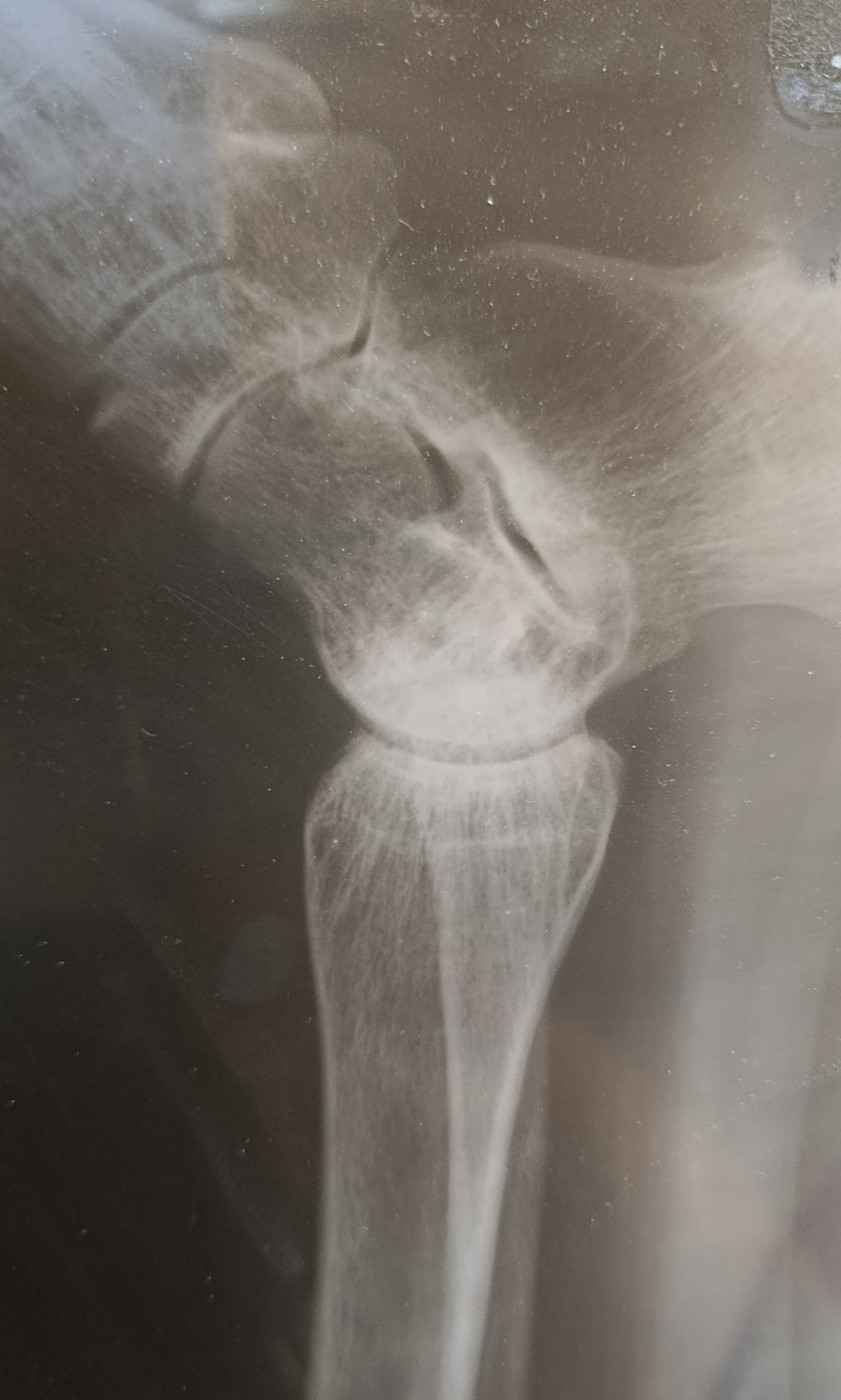

Вывих правой стопы снаружи и сзади, перелом обеих лодыжек и заднего края большеберцовой кости правой голени

Коленный сустав